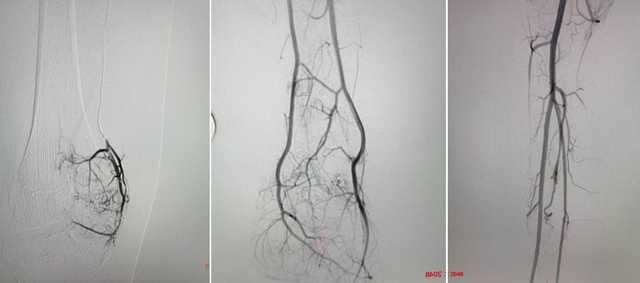

2022年暑假期间,郴州市第一人民医院儿童医院儿童心胸血管中心李思副主任医生为小敏进行了介入栓塞治疗。

动脉造影检查:是诊断本病的主要影像学检查方法,可显示动静脉瘘病变的主要部位、范围以及分流量的大小。

对微小的动静脉瘘常需 行双侧肢体步进动脉造影检查以对照观察患肢的血液动力学异常改变。

动脉造影的主要 X 线征象为:(1)患肢动脉主干增粗血流加快;

(2)动脉分支增多、紊乱、扭曲,常为多发性;

(3)动脉分支的末梢可见毛细血管过早显影染色较深,并可见静脉早期显影现象,但未见直接瘘道。